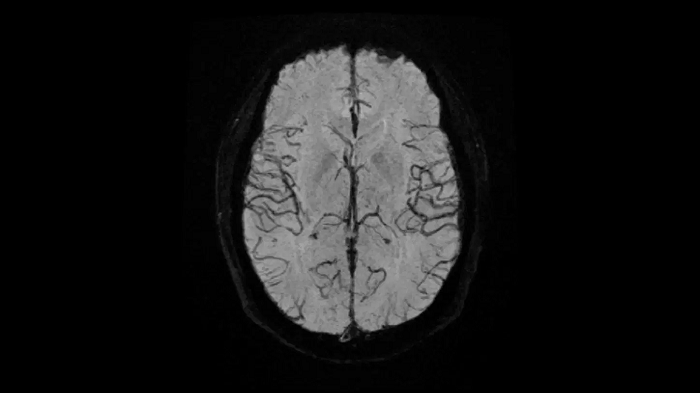

Head

EPI-based 3D SWI

A new approach towards susceptibility-weighted imaging founded on 3D EPI allows highly resolved and high-quality depiction of cranial veins on MAGNETOM Free.Max.

Image Courtesy: University Hospital Erlangen, Germany | Image-ID: 4aaaa0297

Time-of-flight angiography

Non-contrast enhanced angiography of the cranial vessels is used to detect vessel occlusions or aneurysms. High-resolution ToF angiography can also show small arteries for subtle diagnoses.

Image Courtesy: University Hospital Erlangen, Germany | Image-ID: 4aaaa0466